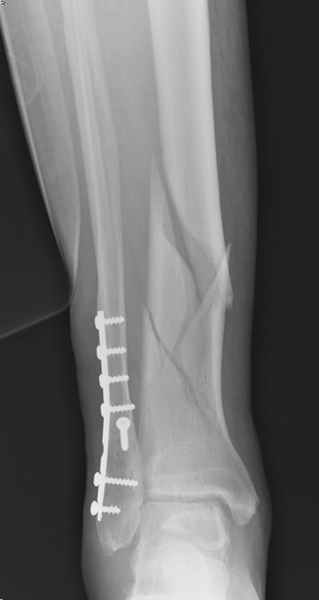

спрашивает что делать с больным который поступил недавно, фермер 55 лет падение при пьяной драке в баре, года два назад перенес операцию на лодыжке, на снимках и КТ перелом без вовлечения сустава,

Повреждение такой локализации, на которой применимы и аппарат (классический Илизарова или гибридный), пластина, особенно Locked Plate, и гвоздь с блокированием. В нашей клинике был бы выполнен закрытый интрамедуллярный остеосинтез. Желательно использовать гвоздь с возможностью провести более чем 2 обычных фронтальных винта в дистальном отломке.

Здесь мы использовали новый Synthes Nail с дополнительными дырками, в проксимальной части 4: по две косых и поперечные (один стандартный а другой динамический), в дистальной части две поперечные, прямая и косая. Вес больного более 120 кг, нагрузку начнем через месяц.

Получилось красиво, поздравляю. Вверху можно было ограничиться одним винтом во фронтальное статическое отверстие, зачем два 45-градусных?

При такий спирали задний край tibia может быть сломан - нет ли этого в данном случае? На всякий случай можно было ввести 1-2 винта 4,5 мм спереди назад мимо гвоздя. Хотя самый дистальный блокирующий винт, возможно, зацепил этот отломок. А какой тут диаметр гвоздя и locking винтов?